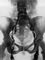

Лимфорентгенографию выполняют прямым (рис.) и непрямым способами. При прямой лимфорентгенографии рентгеноконтрастное вещество вводят непосредственно в просвет предварительно окрашенного (путем подкожного введения красителя) и выделенного через кожный разрез лимфатического сосуда с помощью специального шприца-автомата. Обычно применяют сверхжидкие масляные рентгеноконтрастные вещества типа майодила. Для исследования только регионарных лимфатических сосудов можно использовать водорастворимые рентгеноконтрастные вещества (триомбраст и др.). Рентгенологическое исследование лимфатических сосудов после введения масляных рентгеноконтрастных веществ проводят через 10—30 мин, а лимфатических узлов — через 24 или 48 ч. При использовании водорастворимых рентгеноконтрастных веществ рентгенографию выполняют сразу же после эндолимфатической инъекции.

В зависимости от области введения рентгеноконтрастного вещества различают нижнюю лимфорентгенографию (введение в лимфатические сосуды нижних конечностей), верхнюю лимфорентгенографию (введение в поверхностные локтевые, поверхностные и глубокие лучевые), фуникулярную шейную и др. Лимфорентгенография с одновременным контрастированием глубоких и поверхностных отделов лимфатической системы носит название многоколлекторной.